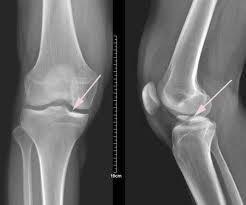

膝關節骨性關節炎多見於中老年女性,會出現骨質增生,即通常所說的長“骨刺”,軟骨退變剝脫會產生游離體,當這些炎性因子刺激膝蓋周圍軟組織時,肌肉會突發痙攣,導致關節發軟,有的活動關節會有摩擦音。嚴重的膝部可出現內翻畸形及內側疼痛。

還有一種發生在年輕人的屬髕骨與股骨之間的軟骨病變,即“髕骨軟化”,由於髕骨軟骨面變得不平,有時伴有先天性的髕骨脫位,會造成軟骨過早退化、缺損,從而使膝關節出現打軟症狀。

“打軟腿”可能是韌帶損傷,需於半月板損傷相鑑別。